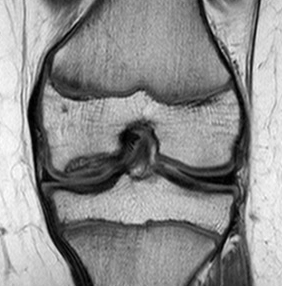

Tunnel view of osteochondritis dissecans

From the collection of H. Chambers, MD